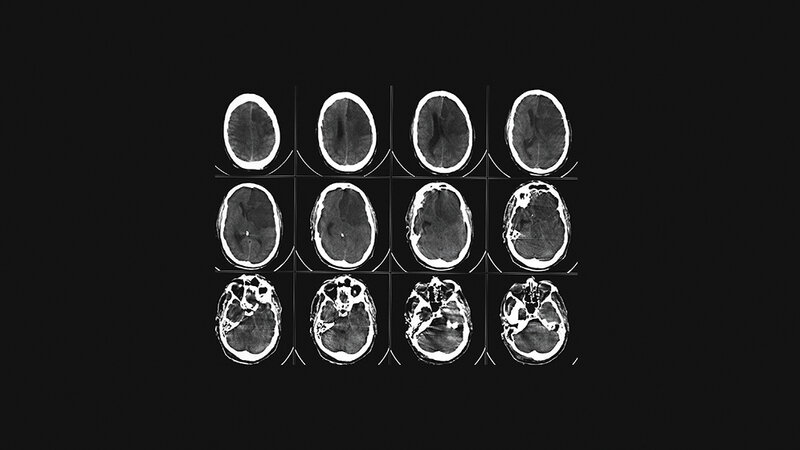

Die dritthäufigste Todesursache in Deutschland ist der Schlaganfall. Jedes Jahr sind Tausende Menschen davon betroffen. Zeit spielt bei diesem Thema die wichtigste Rolle überhaupt, denn es geht um nichts Geringeres als um das Gehirn des Menschen, dem Ursprungsort des Denkens, des Fühlens, der Persönlichkeit jedes Einzelnen. Symptome treten häufig unspezifisch auf, werden nicht rechtzeitig erkannt und mitunter unterschätzt. Hängende Mundwinkel, Wortfindungsstörungen, die Zeitung nicht richtig lesen können, sich komisch fühlen, plötzliche Kopfschmerzen oder für einen Moment nicht wissen, wo man sich befindet. Schon Minuten bis wenige Stunden nach Auftreten der ersten Symptome können bleibende Schäden zurückbleiben oder gar der Tod eintreten. Auf dem schnellsten Weg muss der Patient in eines der zertifizierten Krankenhäuser gebracht werden, um keine Zeit zu verlieren. Die Radiologische Diagnostik spielt eine immense Rolle. Deutschland ist mit etwa 350 zertifizierten Stroke Units flächendeckend gut aufgestellt, dennoch muss ständig an einer Verbesserung gearbeitet werden. Die Computertomografie ist bei den bildgebenden Verfahren noch die Untersuchungsmethode der ersten Wahl, da sie schnell verfügbar und von den meisten technischen Mitarbeitern bedient werden kann. Das MRT bietet hier zwar Vorteile in Bezug auf die Sensitivität, jedoch bilden die Liegezeiten, der Zustand des Patienten und die Erfahrung in der Auswertung und Bedienung, vor allem im Bereitschaftsdienst auf technischer und ärztlicher Ebene, große Hürden.